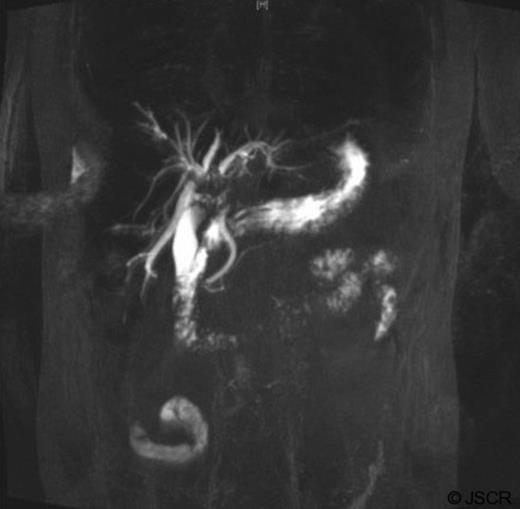

Tumour markers revealed elevated carbohydrate-antigen 19-9 at 807kU/L (normal <40kU/L) suggesting bile-duct disease (1) whilst α-fetoprotein was 4kU/L, within normal range. Magnetic resonance Cholangiopancreatography (MRCP) indicated filling defects in right and left bile ducts (figure 2) and portal vein thrombosis.

The mass had mild hyperintense signal on T2-weighted images and capsule retraction, suggesting a scirrhous lesion (figure 3); possibly cholangiocarcinoma.

T2 weighted abdominal MRI, coronal view displaying right lobe liver mass.